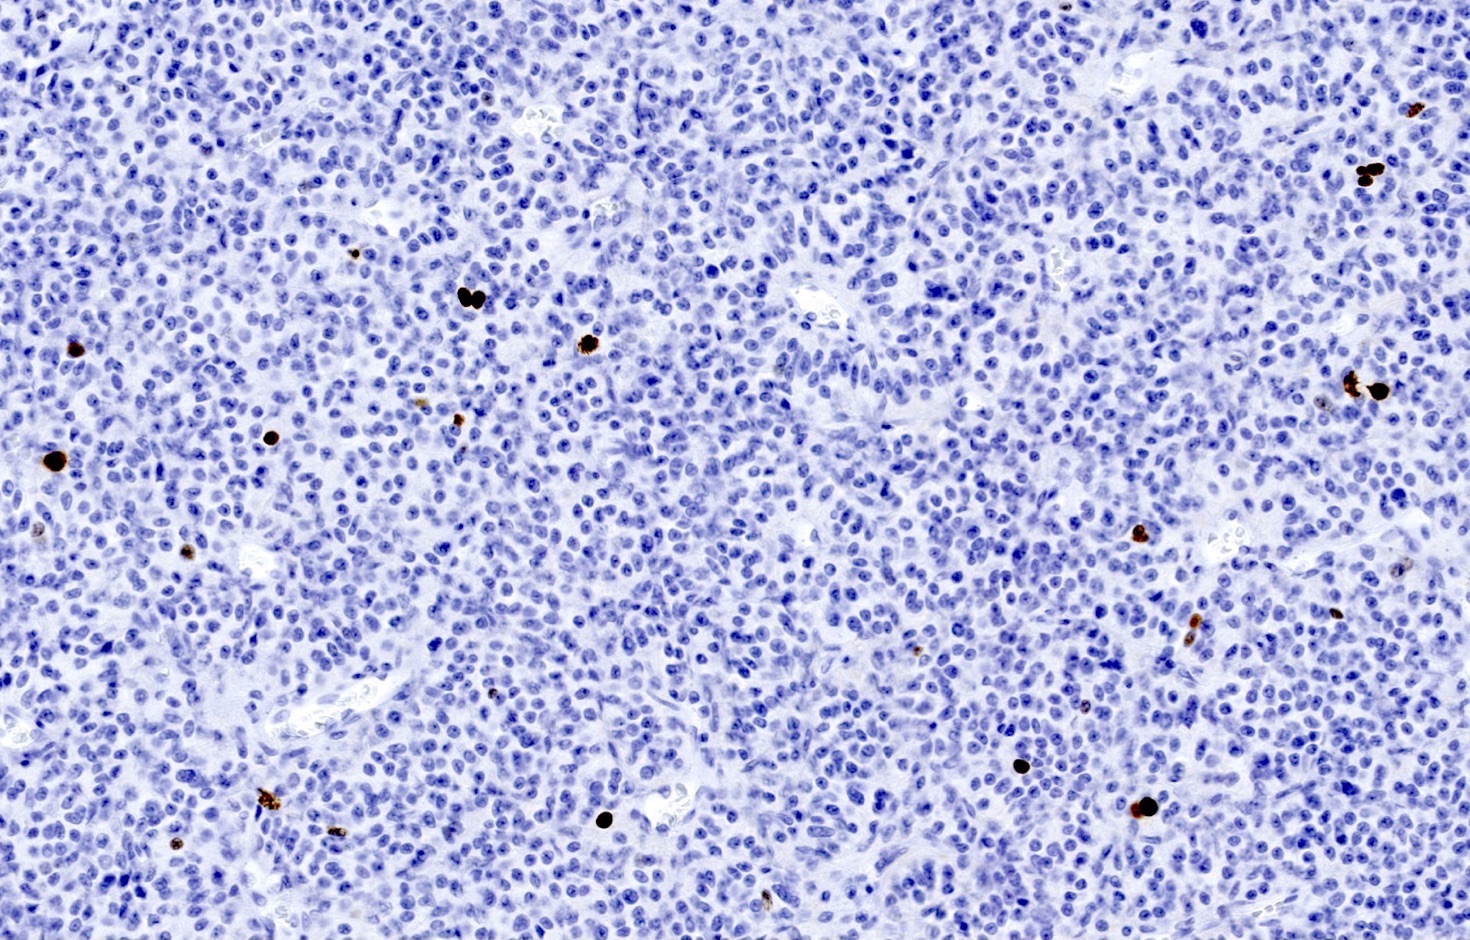

Contributed by Philippe Joubert, M.D., Ph.D., Jijgee Munkhdelger, M.D., Ph.D. and Andrey Bychkov, M.D., Ph.D.

- Chromogranin, synaptophysin, CD56 and INSM1: diffusely and strongly positive (Mod Pathol 2019;32:100)

- Ki67 (expected < 20%)

- Ki67 proliferative index does not have an impact on tumor classification; WHO classification states that is desirable to routinely report its value

- Mostly useful to discriminate between high grade neuroendocrine tumors (small cell carcinoma and large cell neuroendocrine carcinoma), on small or crushed biopsies in particular (Arch Pathol Lab Med 2018;142:947)

- Utility of differentiation between typical and atypical carcinoid is not proven (Virchows Arch 2017;470:153)